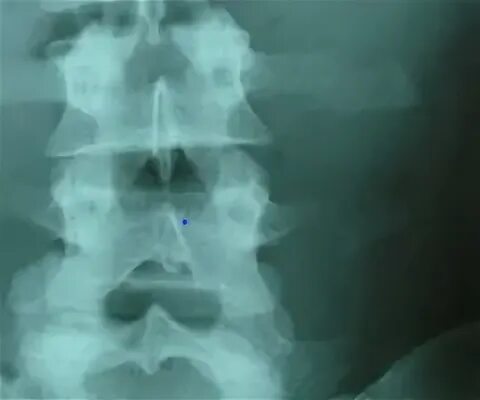

Перелом отростка l2